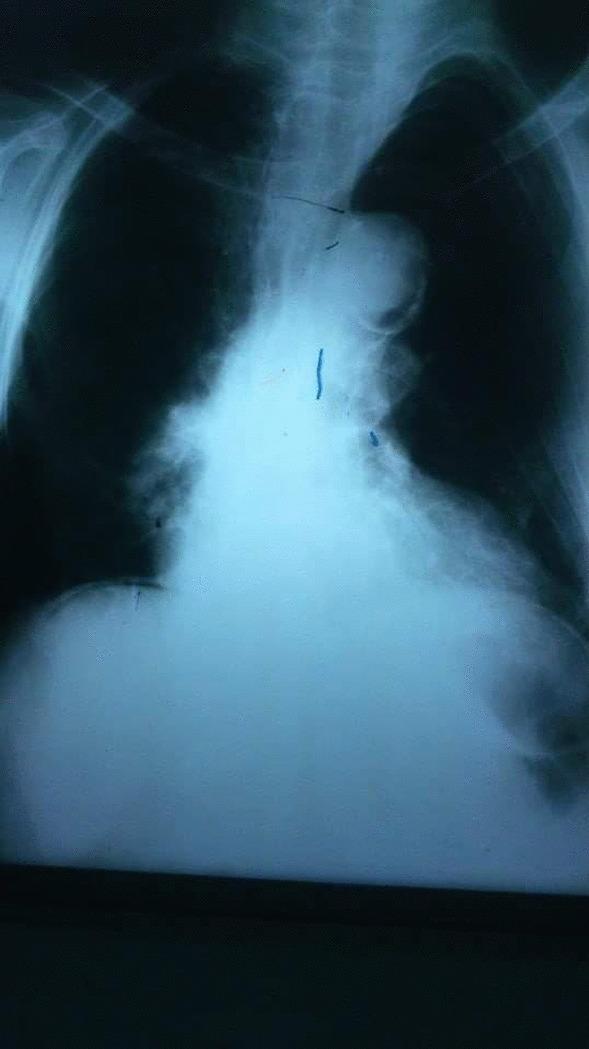

CASE PRESENTATION

This is a case report of an 84-year-old female who presented with an acute surgical abdomen. An exploratory laparotomy revealed complicated small bowel diverticula with a jejunal diverticulum perforation, for which a diverticulectomy was performed.

病例介绍

这是一例 84 岁女性的病例报告,表现为急性外科腹痛。剖腹探查显示复杂的小肠憩室,伴有空肠憩室穿孔,行憩室切除术。